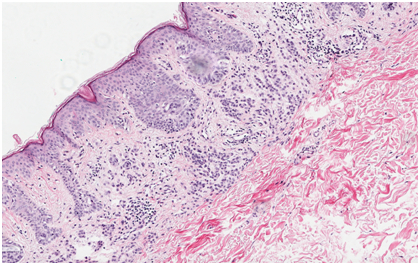

Following institutional review board-authorization, 13 primary cutaneous melanomas and 19 nevi were retrieved (5 common nevi, 5 mild dysplastic, 4 moderate dysplastic, and 5 severe dysplastic), (Figures 1-3). 5-μm formalin-fixed, paraffin-embedded sections were cut and mounted onto positively charged slides. Single IHC S100A9 staining was performed using the Leica Bond III protocol. All antibodies were purchased from Leica Biosystems (Buffalo Grove, IL). A board certified dermatopathologist evaluated S100A9 staining of melanocytes and keratinocytes in the epidermis of each sample. The pattern of staining was classified according to one of three categories: diffuse epidermal staining Figure 4, linear basement membrane staining Figure 5, and irregular patchy epidermal staining Figure 6.

Figure 3 H&E stain of compound nevi of lesion C(hematoxylin and eosin, 40x).

Figure 6 Irregular S100A9 stain of compound nevi of lesion C.